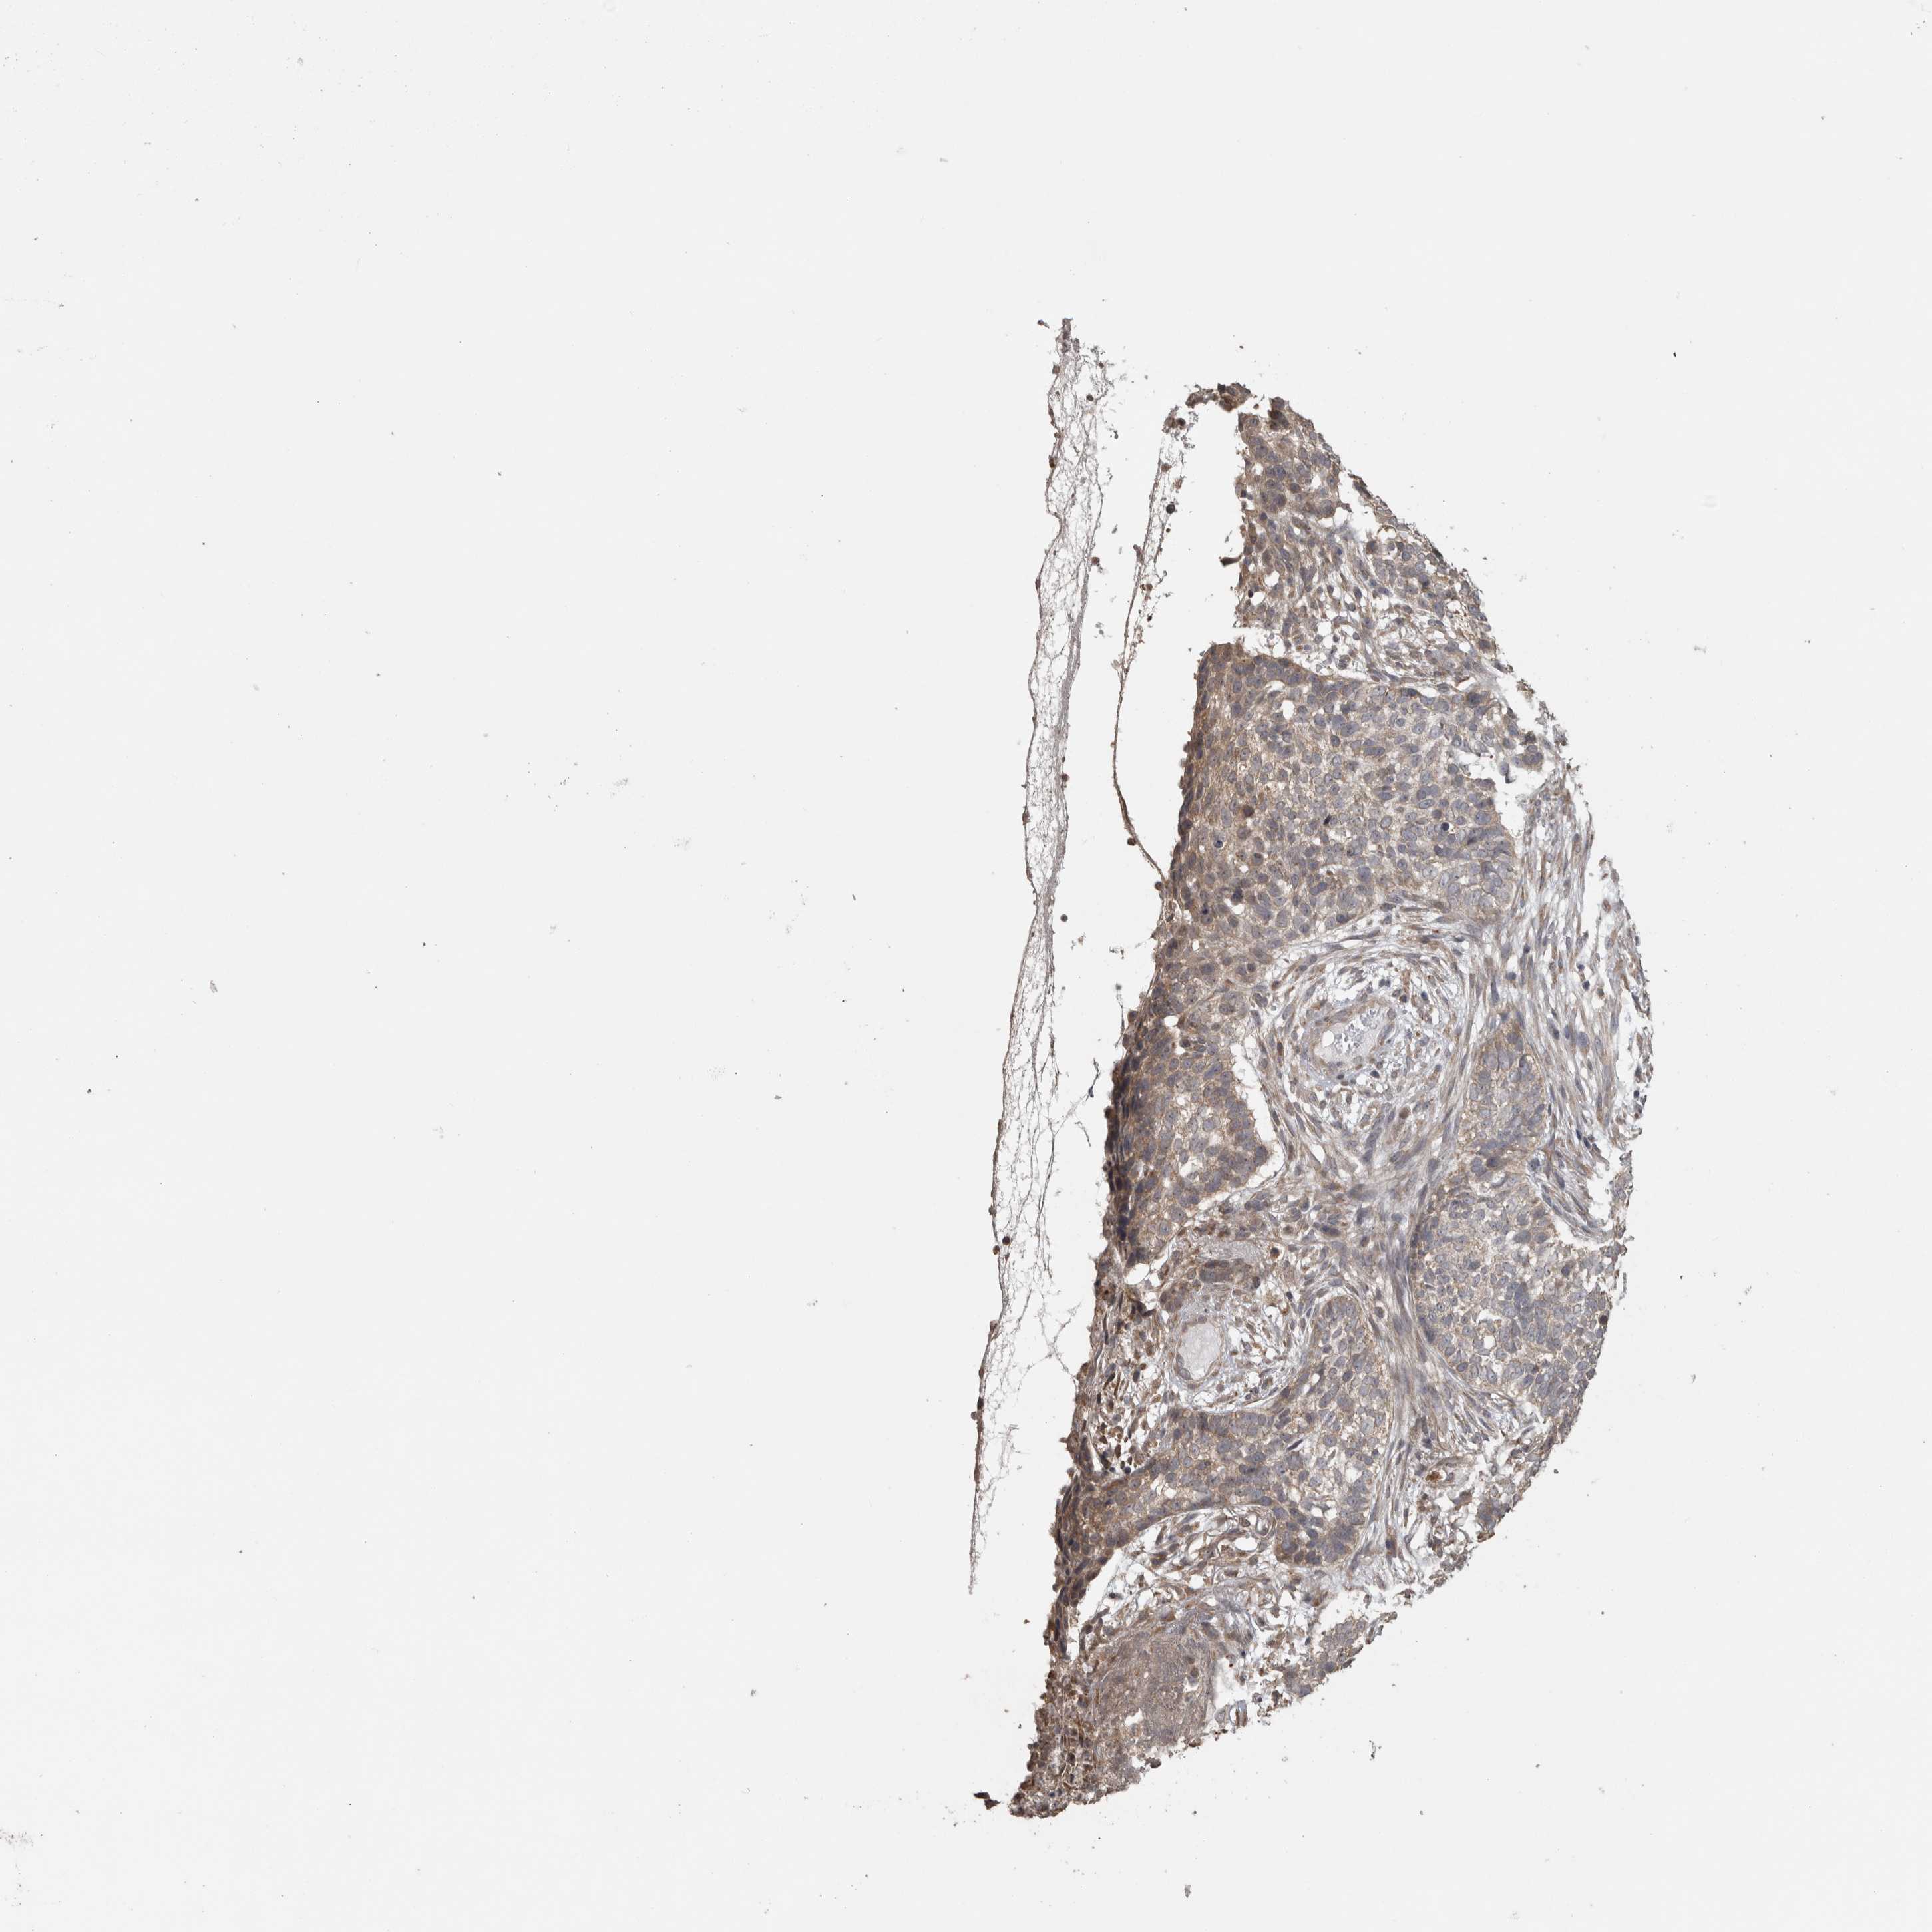

SKIN CANCER - Protein expressioni

A mouse-over function shows sample information and annotation data. Click on an image to view it in a full screen mode. Samples can be filtered based on level of antibody staining by selecting one or several of the following categories: high, medium, low and not detected. The assay and annotation is described here.

Each image is clickable and will lead to virtual microscopy that enables deeper exploration of all samples and also displays staining intensity scores, fraction scores and subcellular localization as well as patient and tissue information for each sample.

Antibody HPA026303

High

Strong

>75%

Location

Basal cell carcinoma